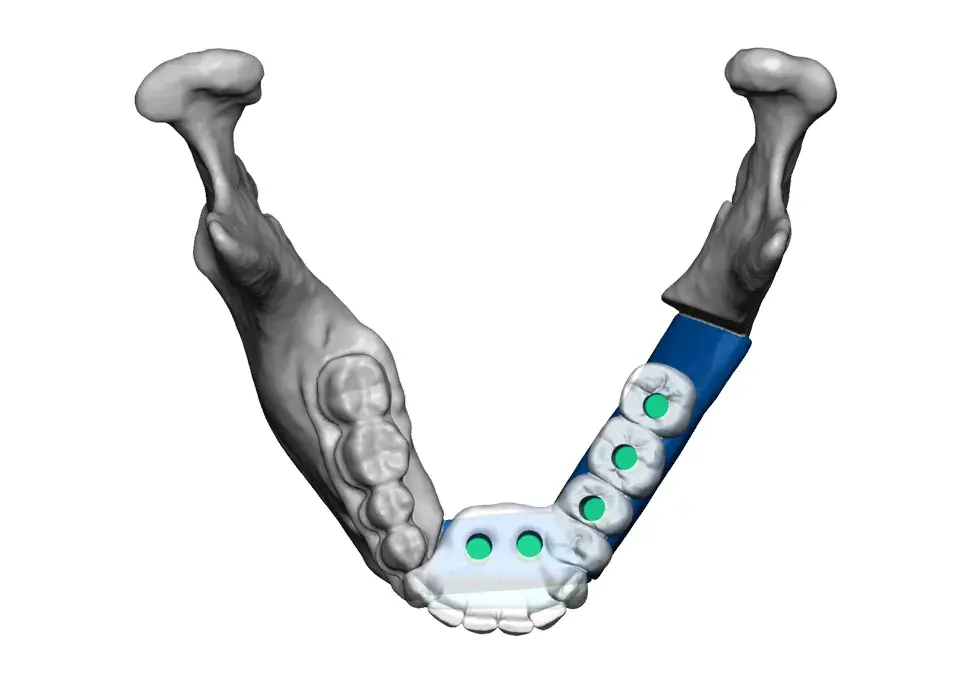

3D Systems' VSP® surgical planning solutions for craniomaxillofacial (CMF) applications received FDA clearance as a service-based approach to personalized surgery over 10 years ago.

3D Systems and Stryker Corporation have partnered to provide surgeons with best-in-class products and services for craniomaxillofacial surgeries. As a leader in personalized healthcare solutions, 3D Systems has planned and delivered devices for more than 140,000 patient-specific cases. The Stryker Craniomaxillofacial business specializes in providing patient-specific options and innovative solutions that help drive efficiencies in surgical suites. The combination of Stryker’s specialized team and advanced implants with 3D Systems' cutting-edge 3D printing technologies and expert consulting services positions both companies to provide a superior level of service to healthcare professionals who use these revolutionary solutions.